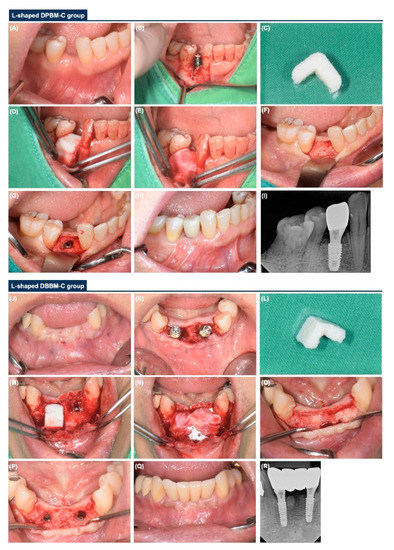

- L-shaped DPBM-C group: DPBM-C (Legograft®, Purgo Biologics, Seongnam, Korea), which was composed of a porcine-derived bone mineral matrix from cancellous bone and 10% atelocollagen from porcine tendon, was directly trimmed to an L-shape using a #15 blade. DPBM-C was manually adapted to the peri-implant dehiscence defect without using additional fixation devices (e.g., bone screws, pins, bone tack, or titanium mesh), and the defect was augmented to ≥1 mm of the buccal and occlusal aspects. The peri-implant dehiscence defect was augmented to ≥1 mm of the buccal and occlusal aspects. The L-shaped DPBM-C was covered with an absorbable native bilayer collagen membrane (NBCM, Geistlich Bio-Gide®, Geistlich Pharma AG, Wolhusen, Switzerland).

- L-shaped DBBM-C group: DBBM-C (Geistlich Bio-Oss® Collagen, Geistlich Pharma AG, Wolhusen, Switzerland) was appropriately trimmed to an L-shape and applied to the peri-implant dehiscence defect. DBBM-C was manually adapted to the peri-implant dehiscence defect without using additional fixation devices, and the defect was augmented to ≥1 mm of the buccal and occlusal aspects. The defects were augmented to achieve a ≥1 mm over-contour for both the buccal and occlusal aspects. Subsequently, the L-shaped DBBM-C was covered with the NBCM.